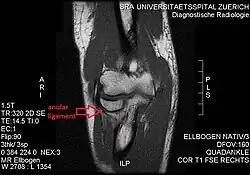

T1 weighted MRI showing the anular ligament